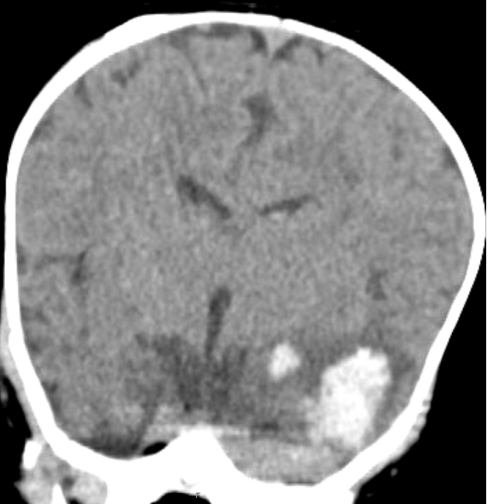

2月龄的木木(化名)突然出现不明原因的呕吐和精神萎靡。在当地医院CT检查提示“左侧颞叶出血”后,不到半天时间,木木的意识便模糊不清并陷入昏迷。

该院神经外科主任医师王超接诊后,第一时间为木木进行详细查体,凭借丰富的临床经验,高度怀疑患儿颅内出血是由血管畸形破裂所致,当即决定联系影像科完善头颅CT及血管成像检查,以进一步明确病因。

“CT检查证实,木木的颅内出血确实源于脑动静脉畸形破裂。”王超表示,“更棘手的是,我们在患儿供血动脉处发现了两个巨大的瘤样鼓包,患儿情况不容乐观。”